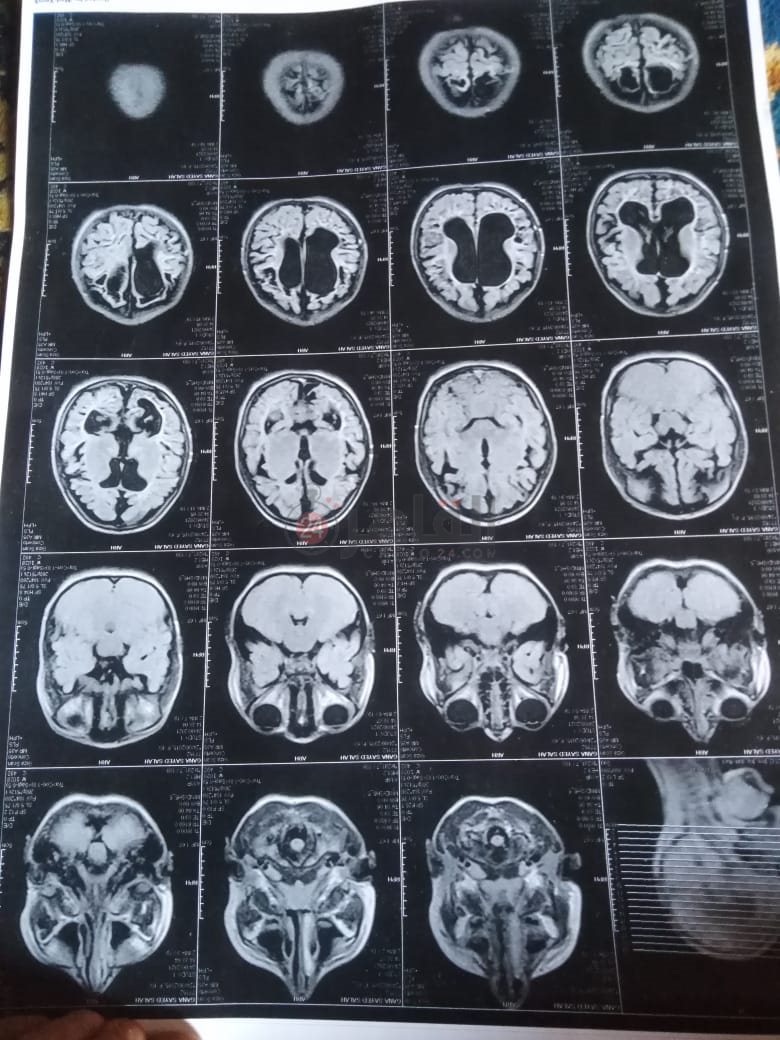

من جانبه، قال صلاح سيد، والد الطفلة جنى صلاح، إن ابنته تعاني من ضمور في المخ منذ ولادتها، نتيجة خطأ طبي، أدى إلى نقص كبير في الأكسجين لديها.

وأضاف في تصريحات خاصة لـ "القاهرة 24": "جنى تبلغ من العمر 6 سنوات، لا تستطيع المشي أو الوقوف على قدميها، نتيجة إصابتها بضمور في المخ منذ ولادتها".

وتابع: "مكنتش بتتحرك خالص، وجسمها طري، روحت كشفت عليها، وعملت أشعة وتحاليل كتير، أتأكدنا إصابتها بضمور في المخ"، مضيفًا:" مش بتعرف تأكل احنا اللي بنأكلها، هي عقلها كويس لكن مش بتتحرك ولا تتكلم".